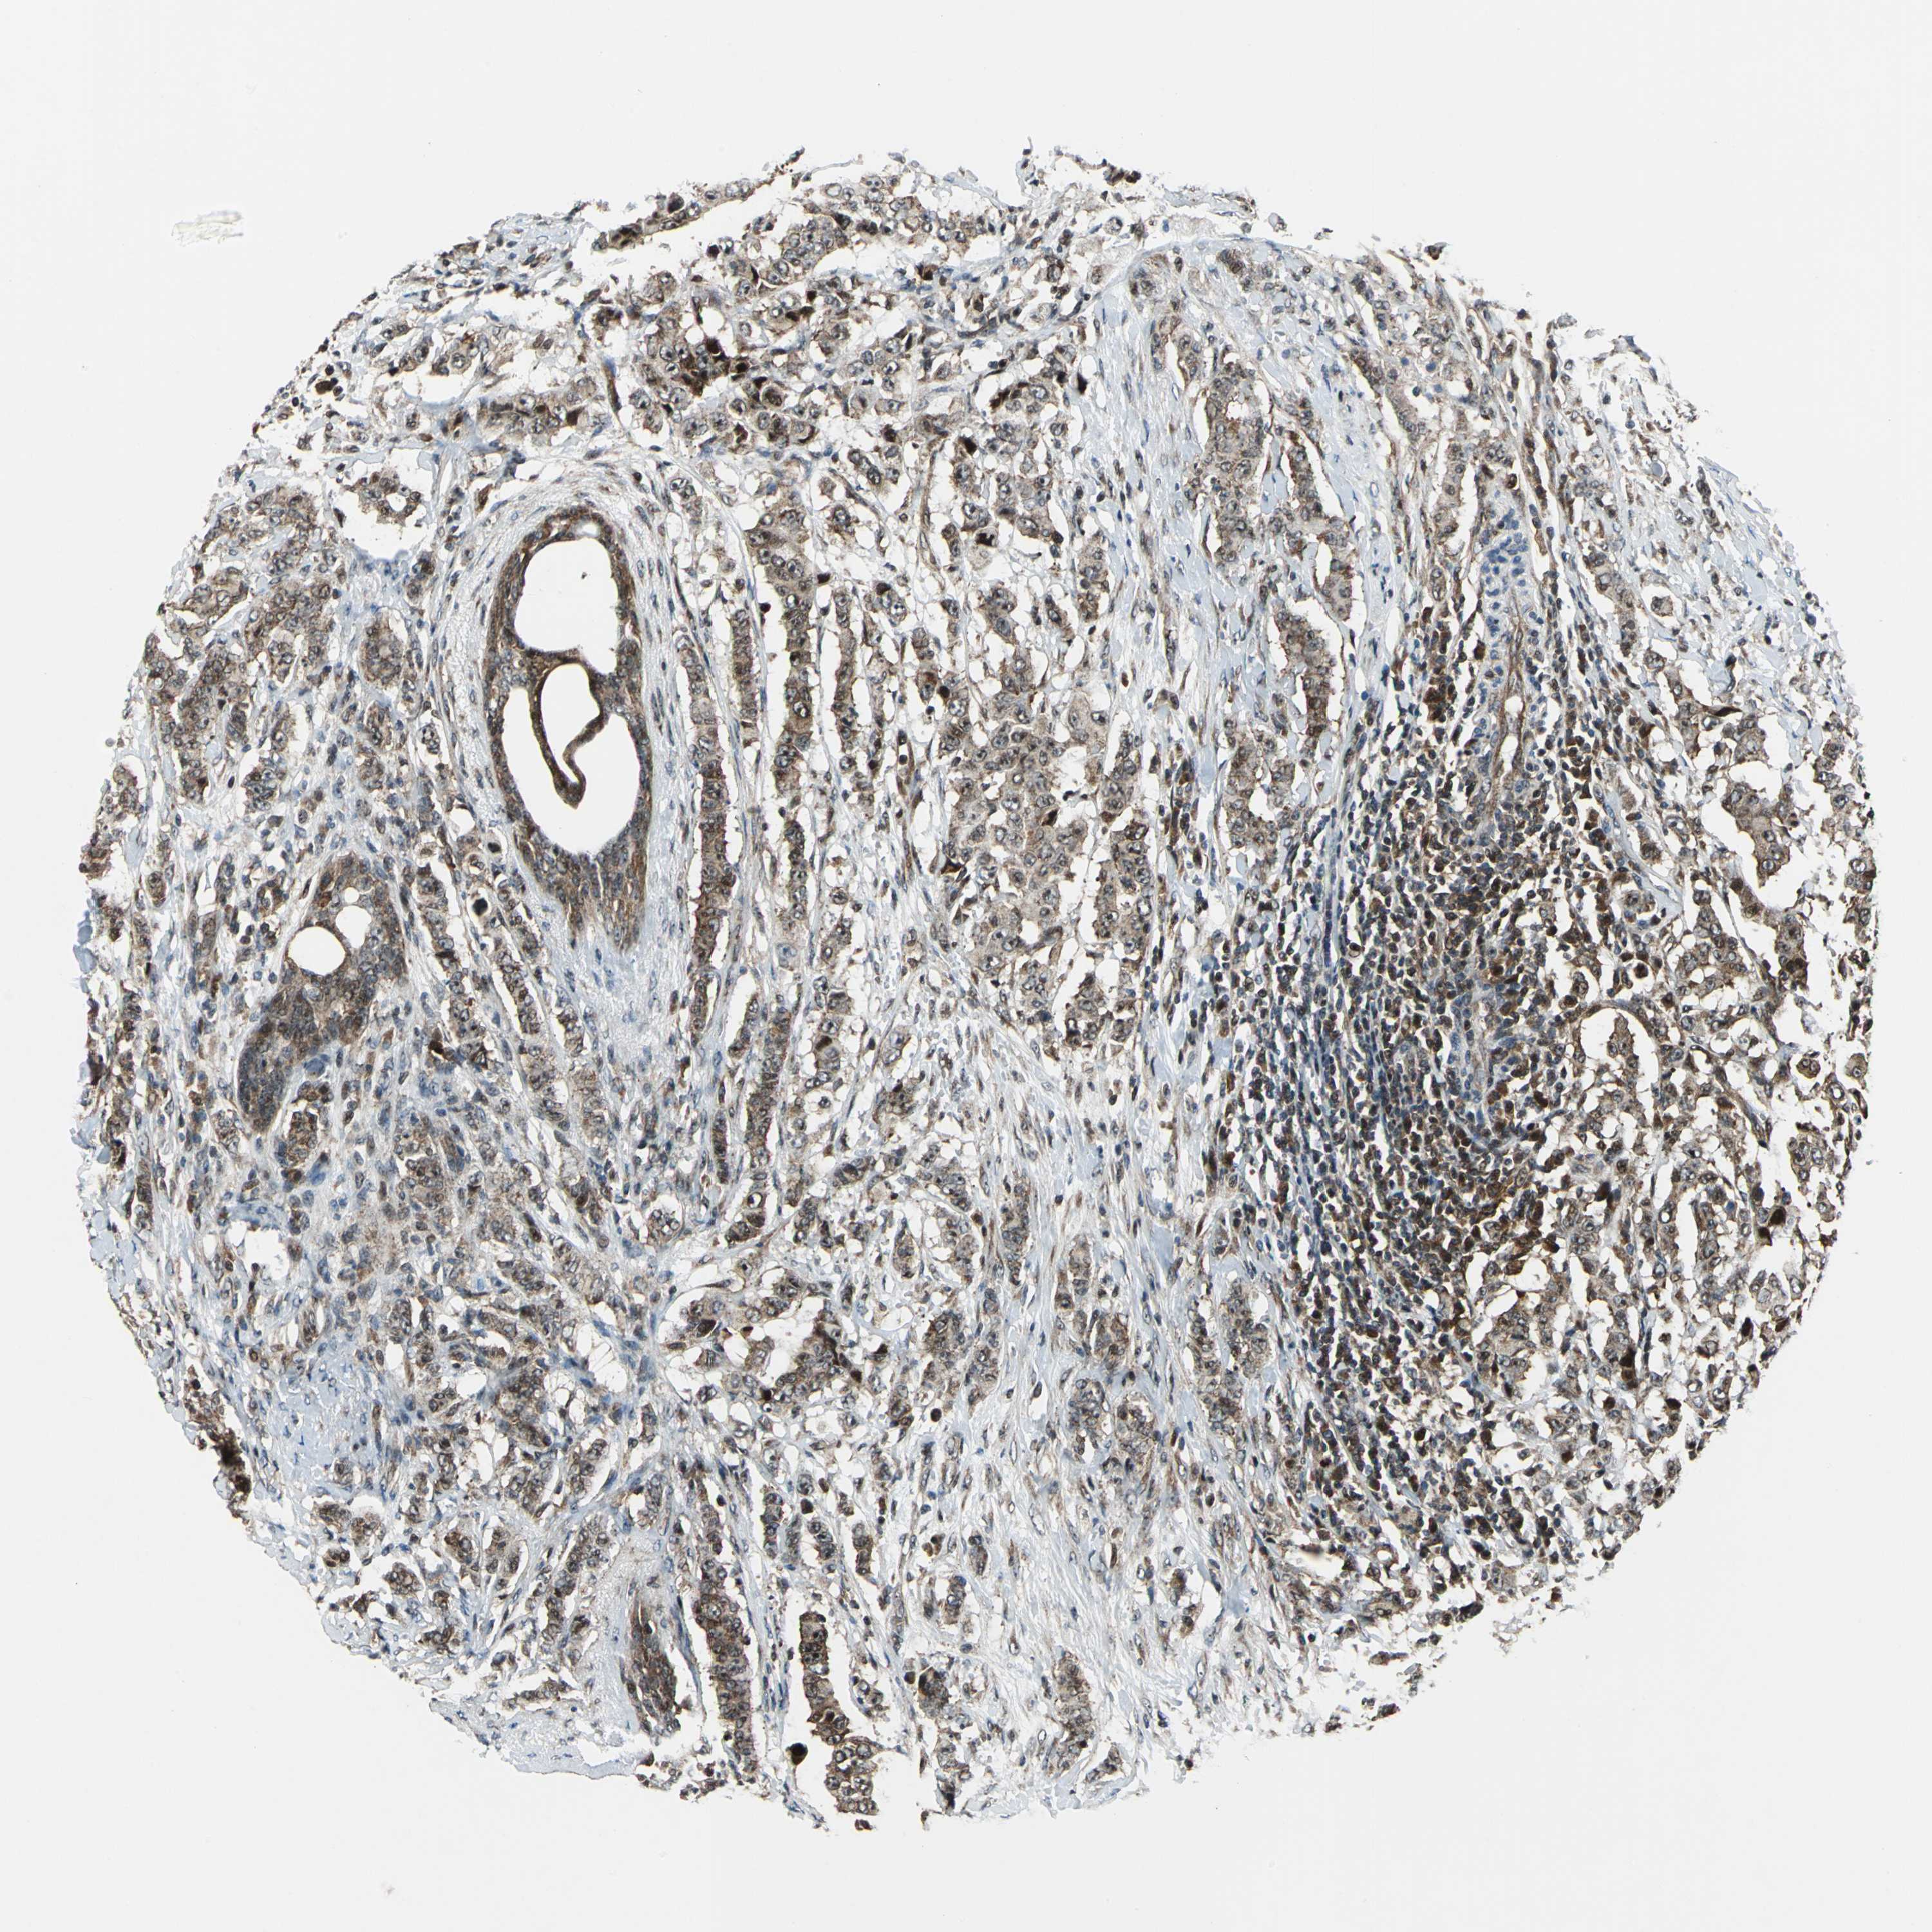

CANCER BREAST CANCER Show tissue menu

BRCA TCGA BRCA VALIDATION PROTEIN EXPRESSION

Breast cancer

Human cancer

AATF is not prognostic in Breast Invasive Carcinoma (TCGA)